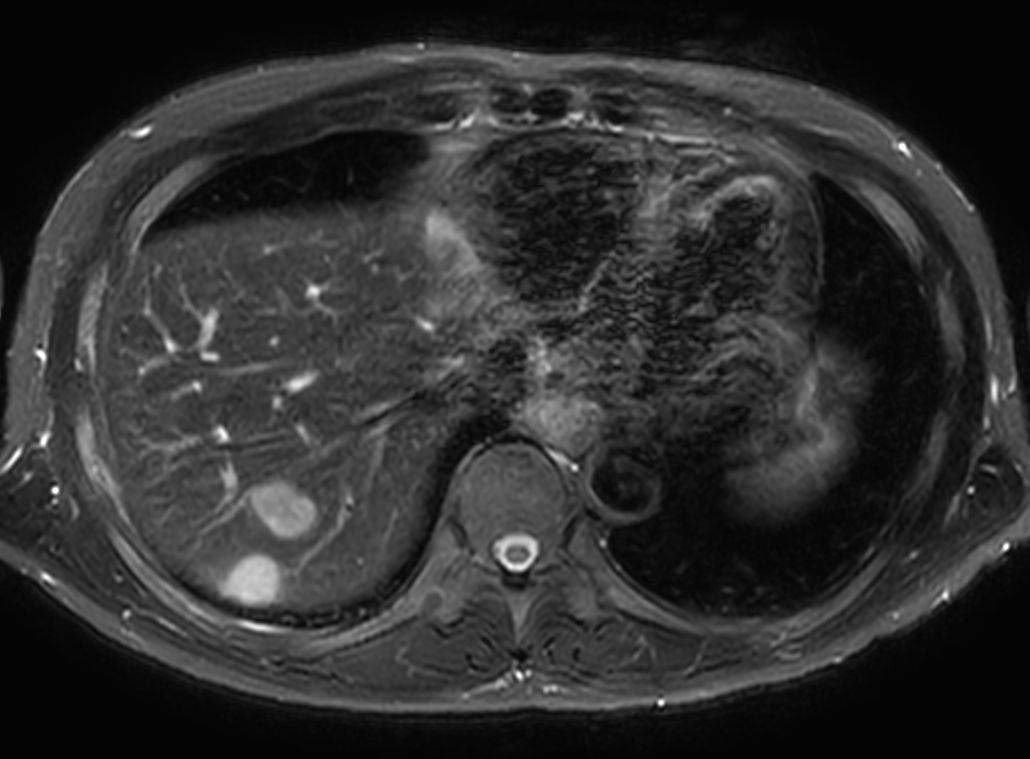

T1w FFE mDIXON XD - Breath hold Compressed SENSE

T1w FFE mDIXON XD - Breath hold (15 min. post-gado) Compressed SENSE